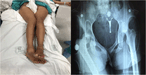

An unusual case of traumatic bilateral hip dislocation without fracture

Andrés Cobar and others

Journal of Surgical Case Reports, Volume 2017, Issue 5, May 2017, rjw180, https://doi.org/10.1093/jscr/rjw180